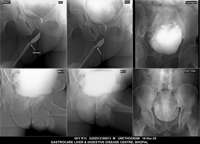

Section: URETHROGRAM

Total: 95 Cases